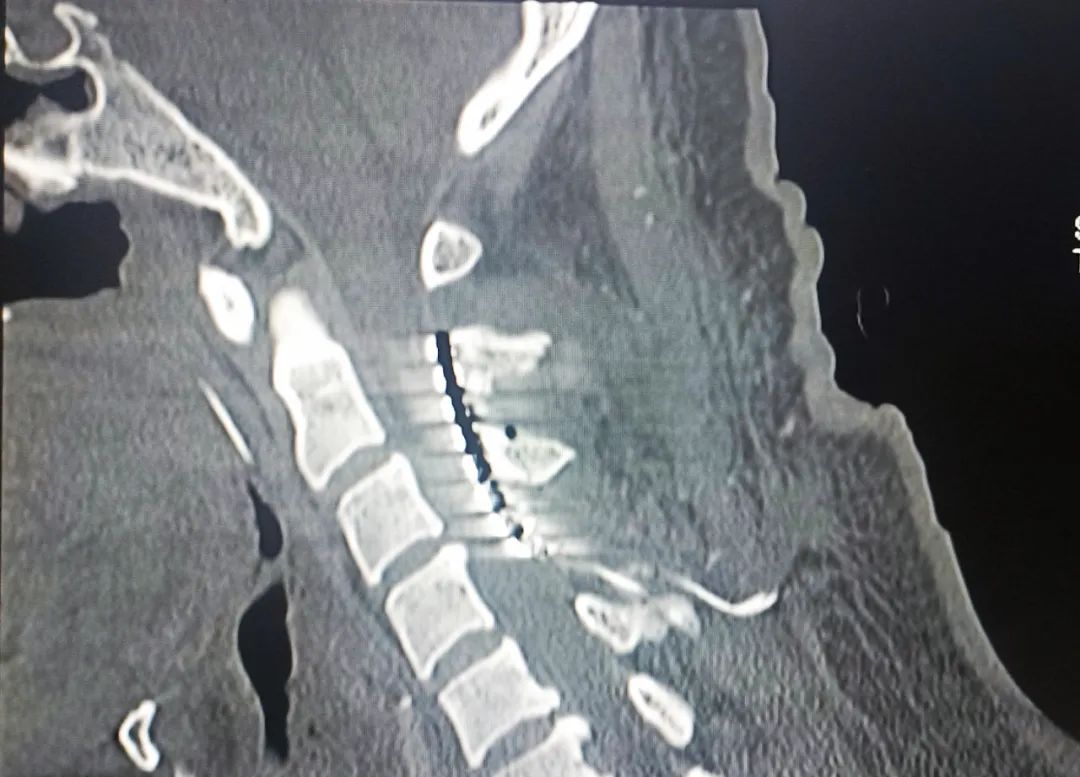

患者,男,37歲,4個(gè)月余前因“腦干出血”入住我院,經(jīng)過(guò)多次搶救治療,雖然保住了患者性命,但一直處于昏迷狀態(tài)。續(xù)繼軍主任和吳開(kāi)福主治醫(yī)師,經(jīng)過(guò)全面評(píng)估及充分的溝通后,對(duì)患者實(shí)施脊髓電刺激手術(shù)促醒治療。該手術(shù)具有創(chuàng)傷相對(duì)小,安全性高,術(shù)后床旁開(kāi)機(jī)程控操作簡(jiǎn)單等優(yōu)點(diǎn)。現(xiàn)術(shù)后開(kāi)機(jī)程控一個(gè)月,患者的意識(shí)障礙及肢體活動(dòng)等情況得到不同程度改善。